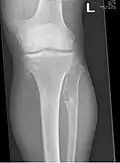

It is characterized by the growth of cartilage-capped benign bone tumours around areas of active bone growth, particularly the metaphysis of the long bones. Typically five or six exostoses are found in upper and lower limbs. Image depicts adult regrowth after knee replacement.

The diagnosis of HMO is based upon establishing an accurate correlation between the above-mentioned clinical features and the characteristic radiographic features. Family history can provide an important clue to the diagnosis. This is supplemented by testing for the two genes in which pathogenic variants are known to cause HMO namely EXT1 and EXT2. A combination of sequence analysis and deletion analysis of the entire coding regions of both EXT1 and EXT2 detects pathogenic variants in 70–95% of affected individuals.[3][7] The hallmark of radiographic diagnosis is the presence of osteochondromas at the metaphyseal ends of long bones in which the cortex and medulla of the osteochondroma represent a continuous extension of the host bone. This is readily demonstrable in radiographs of the knees.[3][1]

Multiple osteochondromas around the knee -